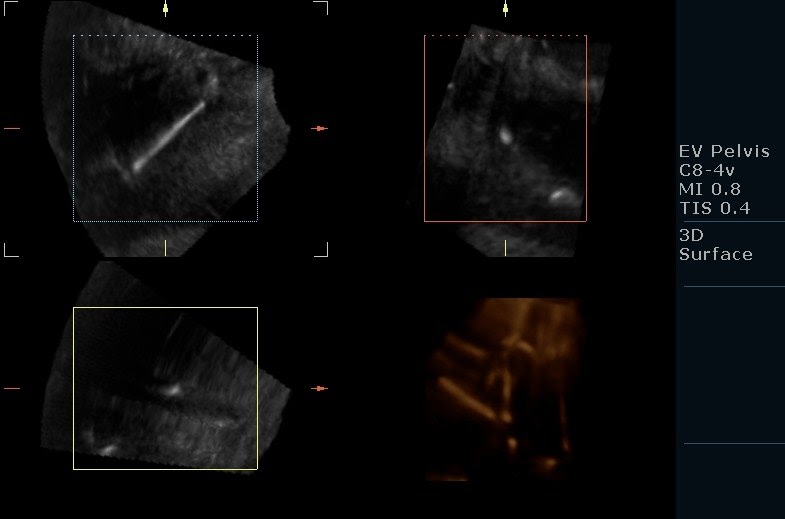

From gynogab.blogspot.com

Copper IUD, spotted in Uterus! Copper Iud Pregnancy Symptoms studies have shown that the risk of miscarriage, preterm birth, and infection of the amniotic sac and fluid before delivery (chorioamnionitis) is. Paragard is an intrauterine device (iud). if you have a hormonal iud and suspect that it’s failed, talk to your doctor about switching to a copper iud. the copper iud (paragard) contains no hormones and. Copper Iud Pregnancy Symptoms.